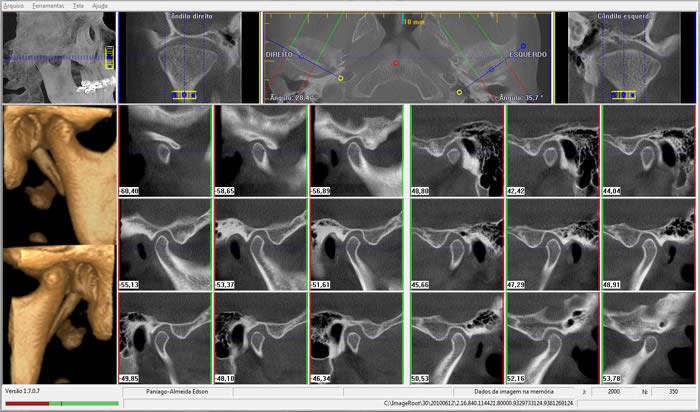

• ATM

Visualização dos componentes ósseos com a maior resolução existente na atualidade.